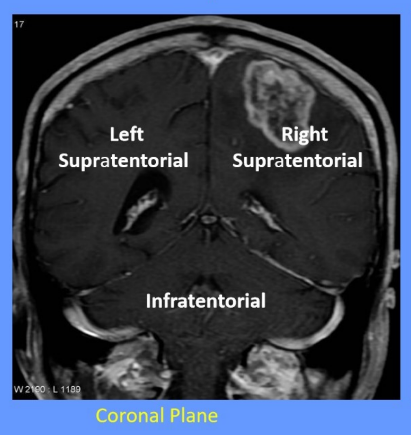

How is the cranial vault divided into compartments?

-divided into 2 continuous compartments by inward folds of the meningeal layer of dura mater

What is the tentorium cerebelli and what does it do

tent shaped fold of dura mater

divides the intracranial cavity into supratentorial and infratentorial compartments

What divides the supratentorial compartment

divided by the falx cerebri into the left and right supratentorial space which can communicate with each other and with the infratentorial space

What is the falx cerebri

vertical fold of the dura mater located in the longitudinal fissure that separates the left and right cerebral hemispheres

Label this image